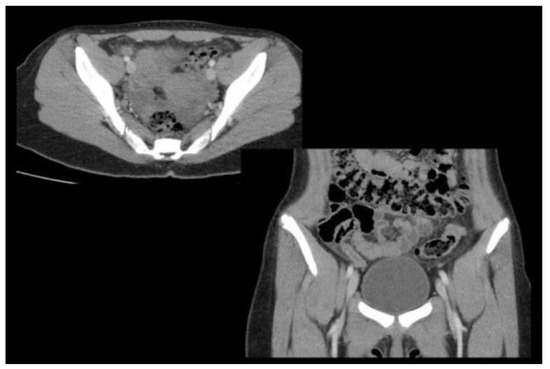

- Old, J.L.; Dusing, R.W.; Yap, W.; Dirks, J. Imaging for suspected appendicitis. Am Fam Physician. 2005, 71, 71–78. [Google Scholar] [PubMed]

- Wonski, S.; Ranzenberger, L.R.; Carter, K.R. Appendix Imaging. In StatPearls [Internet]; StatPearls Publishing: Treasure Island, FL, USA; Available online: https://www.ncbi.nlm.nih.gov/books/NBK549903/ (accessed on 17 April 2023).

- Foley, W.D. CT Features for Complicated versus Uncomplicated Appendicitis: What Is the Evidence? Radiology 2018, 287, 116–118. [Google Scholar] [CrossRef]